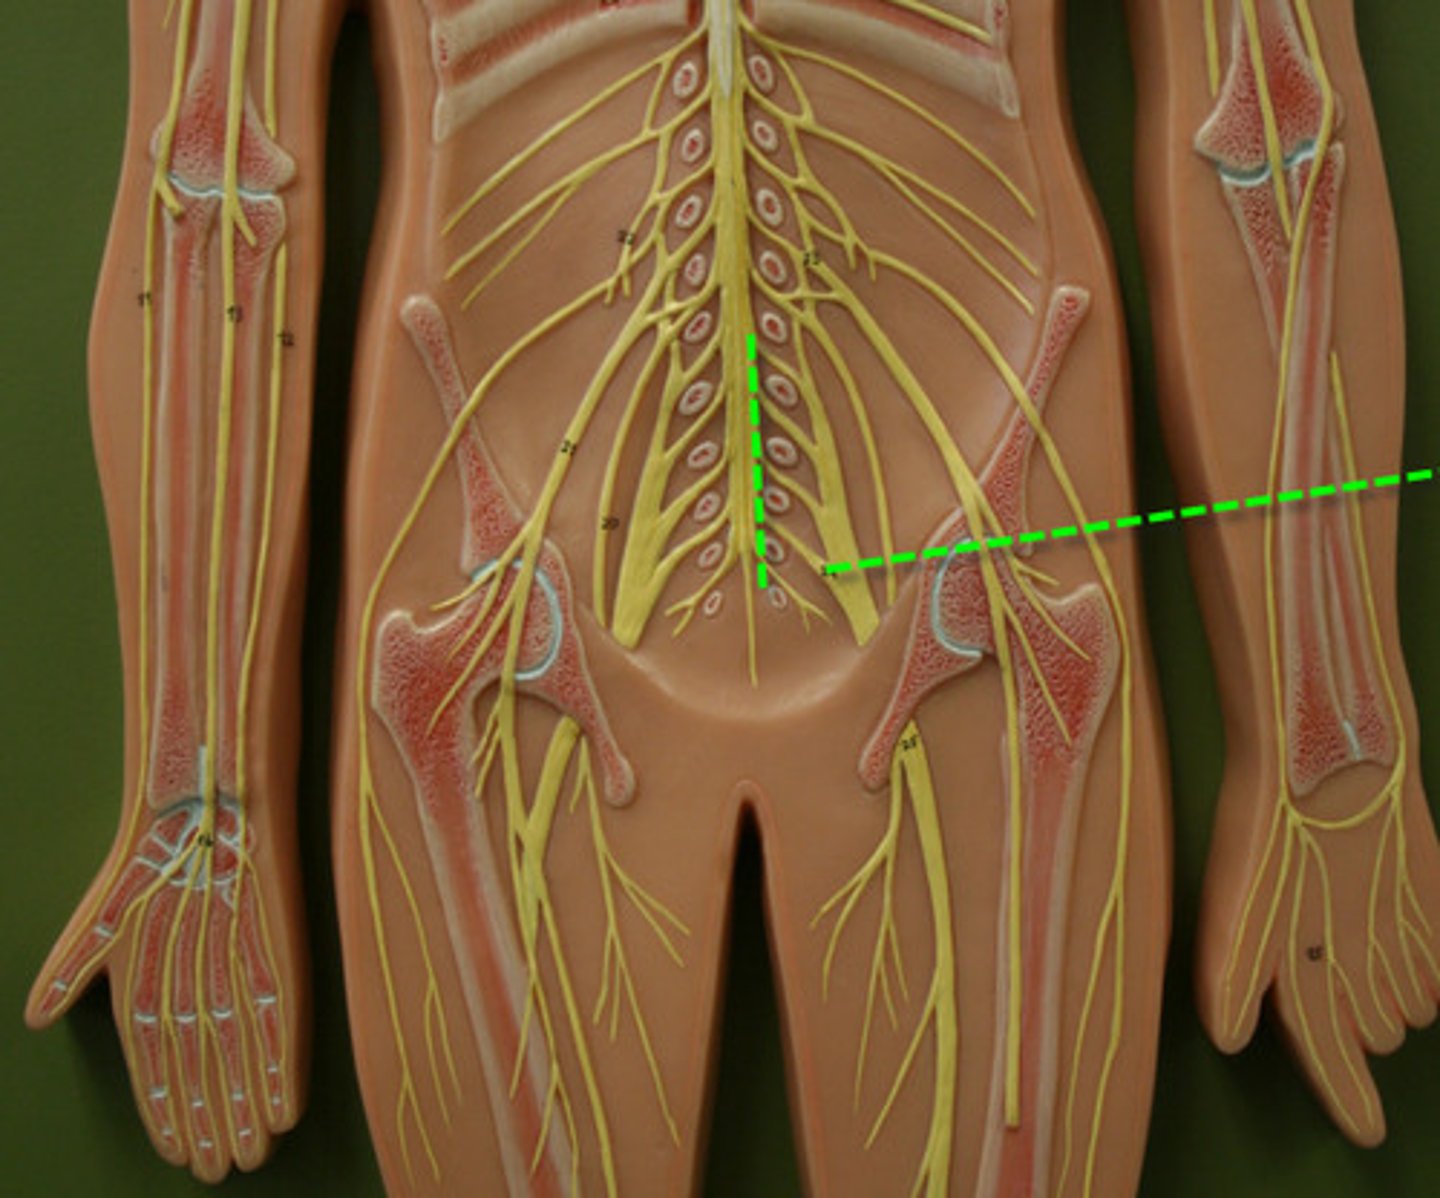

cervical plexus

C1-C5

brachial plexus

C5-T1

lumbar plexus

T12- L4

sacral plexus

L4- S4

genitofemoral nerve

Wishbone of the leg

lateral femoral cutaneous nerve

femoral nerve

saphenous nerve

posterior femoral cutaneous nerve

sciatic nerve

obturator nerve

common fibular nerve

tibial nerve